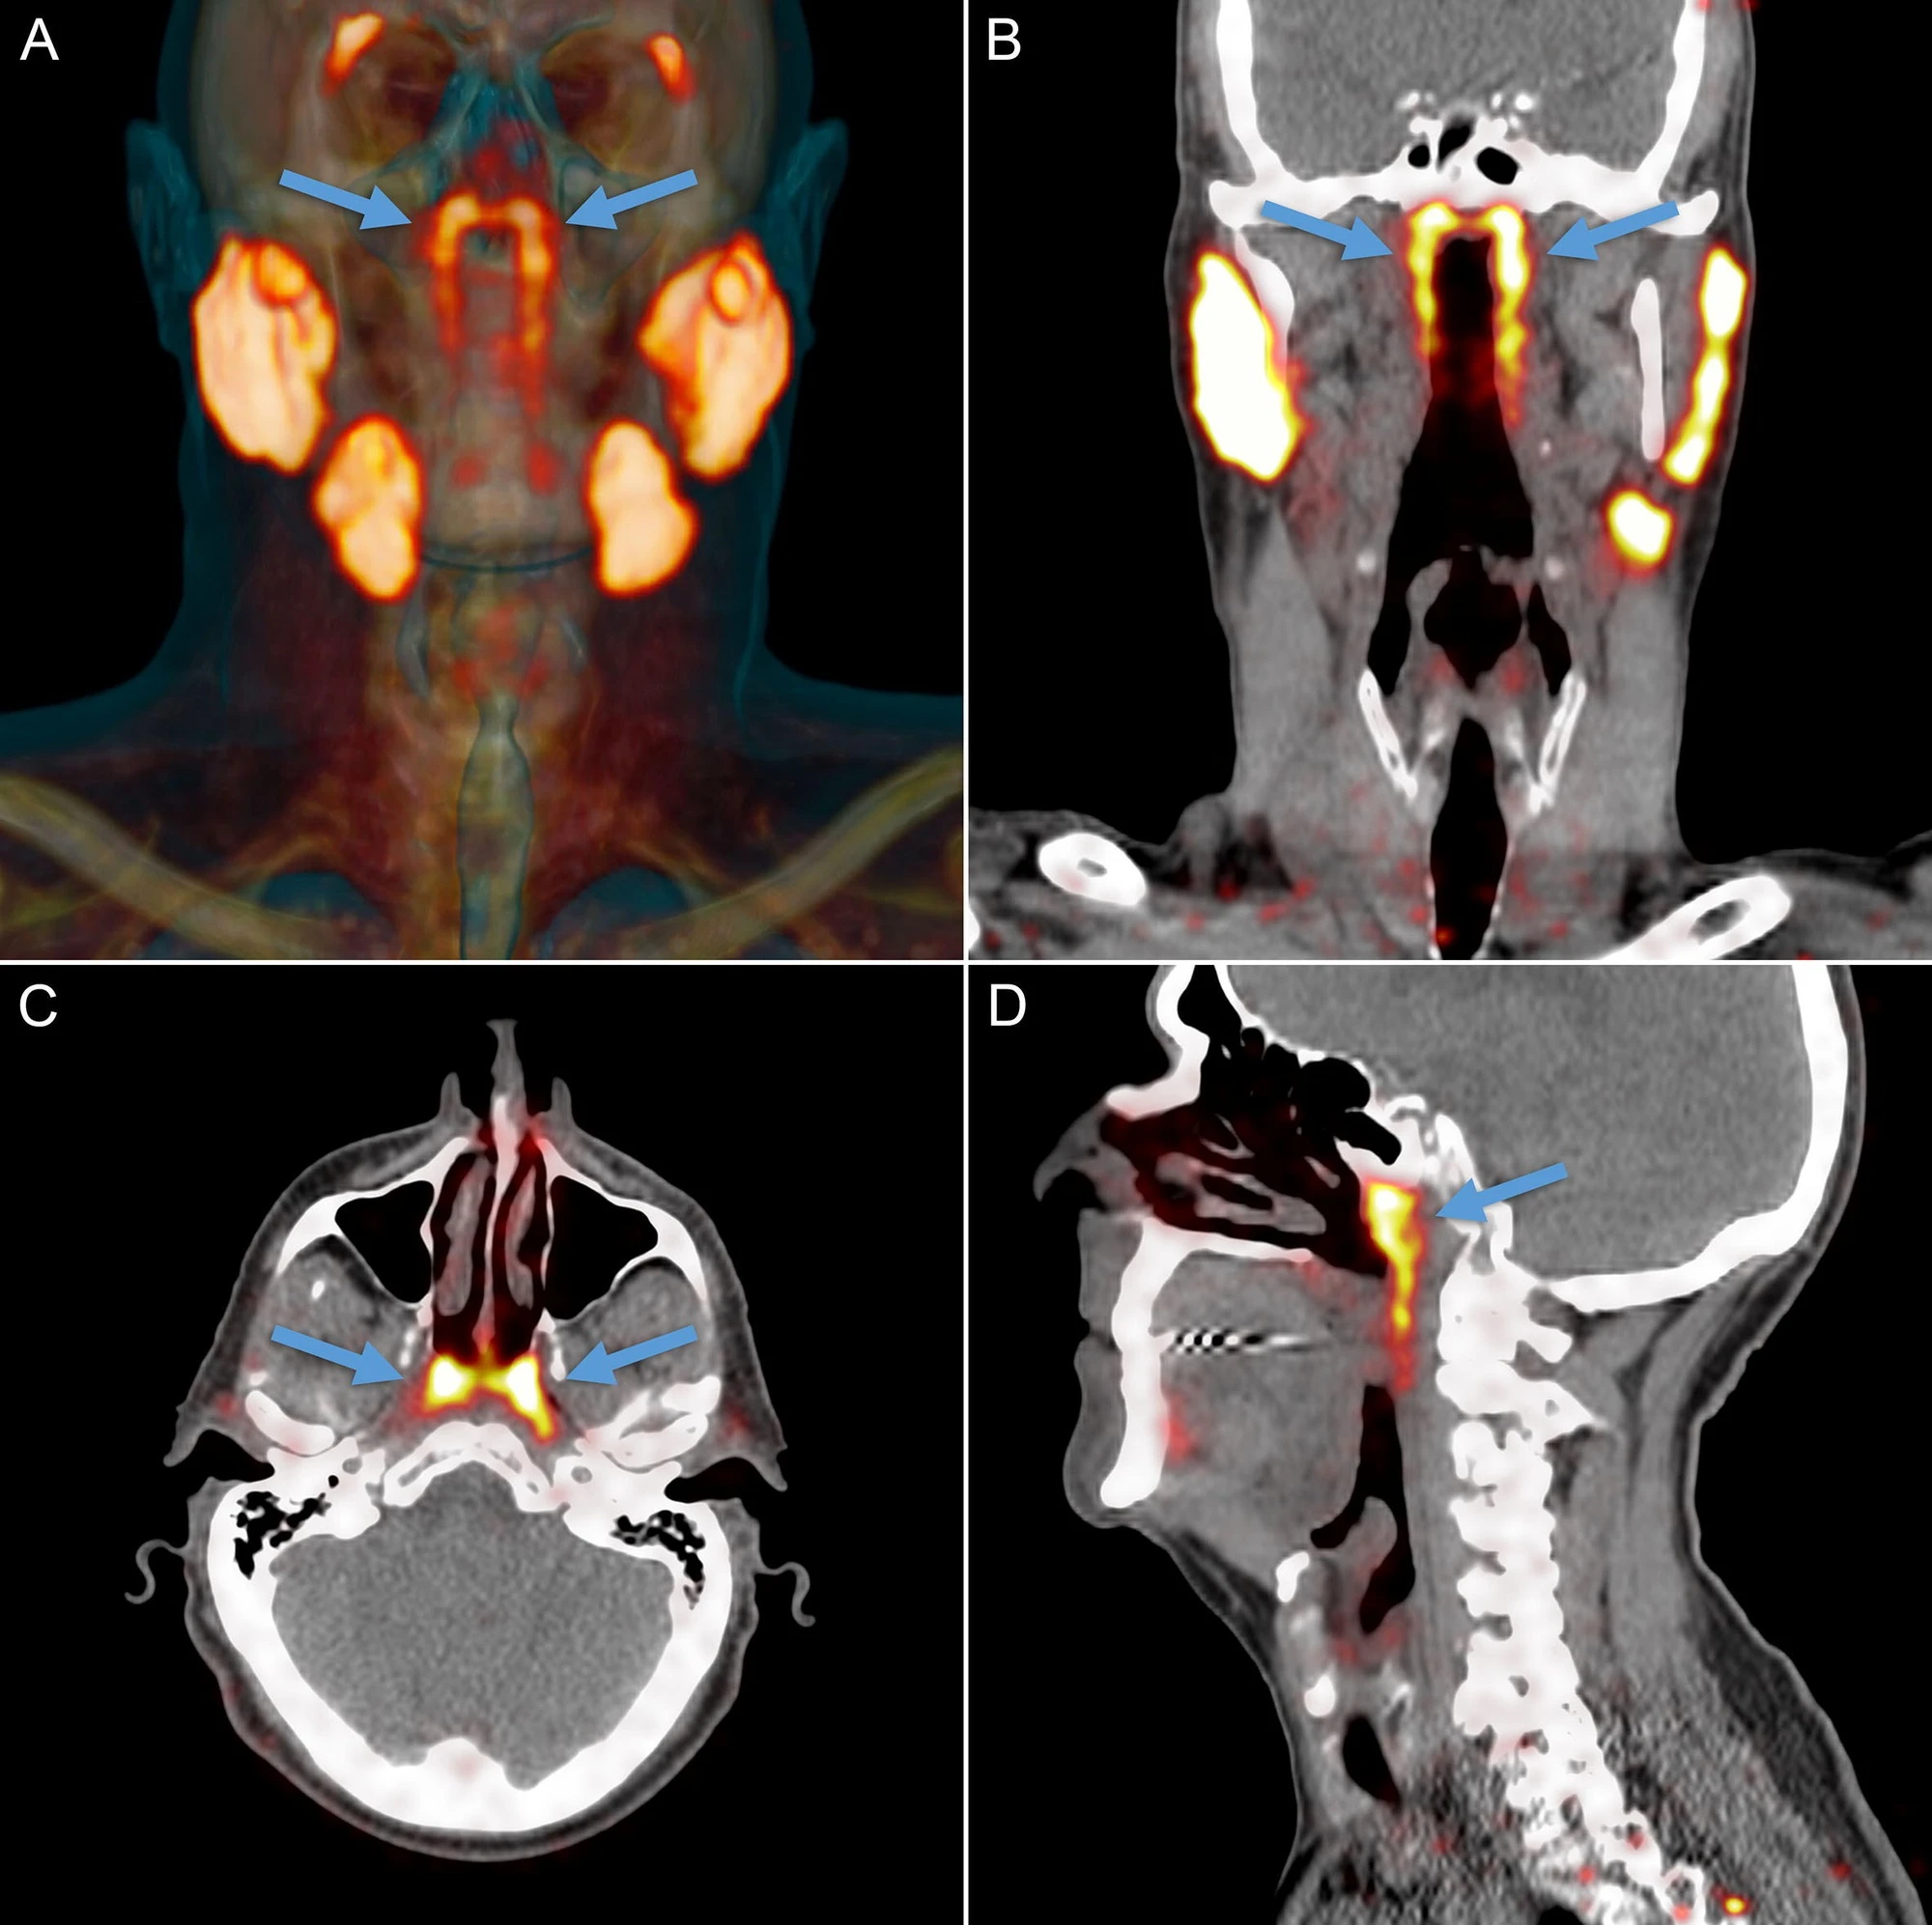

Theo PubMed, vào năm 2020, các nhà nghiên cứu Hà Lan công bố phát hiện một cặp tuyến nước bọt mới nằm ngay phía sau mũi, trong khu vực nối giữa khoang mũi và họng. Sau đó, nó đã được các chuyên gia đặt tên là tuyến nước bọt ống hầu (tubarial salivary glands). Phát hiện này lập tức làm dậy sóng truyền thông và cộng đồng khoa học vì nếu đúng, nó sẽ bổ sung vào “bản đồ” giải phẫu người vốn tự hào có 3 cặp tuyến nước bọt lớn đã được biết đến lâu nay.

Theo NKI, câu chuyện bắt đầu không phải từ phòng mổ giải phẫu mà từ… máy PET/CT cho bệnh nhân ung thư tiền liệt tuyến. Khi các bác sĩ tiêm chất đánh dấu và soi hình ảnh, họ thấy hai vùng sáng bất thường ở vòm họng xuất hiện nhất quán trong hàng loạt bệnh nhân đã gợi ý có một cấu trúc tuyến lớn hơn những “tuyến nhỏ rải rác” mà sách y đã mô tả trước đó. Khám nghiệm thêm trên xác và phân tích mô cho thấy tồn tại mô tuyến với nhiều ống dẫn, đủ để các tác giả đặt vấn đề đây là một “vùng tuyến” có thể coi là cơ quan.